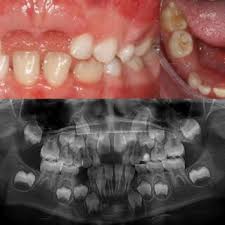

2. 치아 및 잇몸 검사: 치과 의사는 환자의 치아와 잇몸을 시각적으로 검사합니다. 이 과정에서 치과 거울과 탐진기(프로브)를 사용하여 치아 주위 잇몸의 충혈, 부풀음, 치아 이동 및 치주주머니의 형성 여부를 확인합니다.

3. 치주주머니 측정: 치주염의 진행 정도를 판단하기 위해 치주주머니의 깊이를 측정합니다. 탐진기를 사용하여 치주주머니의 깊이를 측정하고, 이것은 치주염의 정도를 판단하는 중요한 지표 중 하나입니다. 정상적인 치주주머니의 깊이는 3 밀리미터 미만이며, 치주염이 진행되면 깊이가 증가합니다.

4. X-레이 검사: 치주염 진단에는 치아 주변 뼈의 손상 정도를 평가하기 위해 X-레이 검사가 사용될 수 있습니다. 이를 통해 의사는 뼈 손상이 어느 정도인지 확인하고 치주염의 정확한 진행 정도를 평가할 수 있습니다.